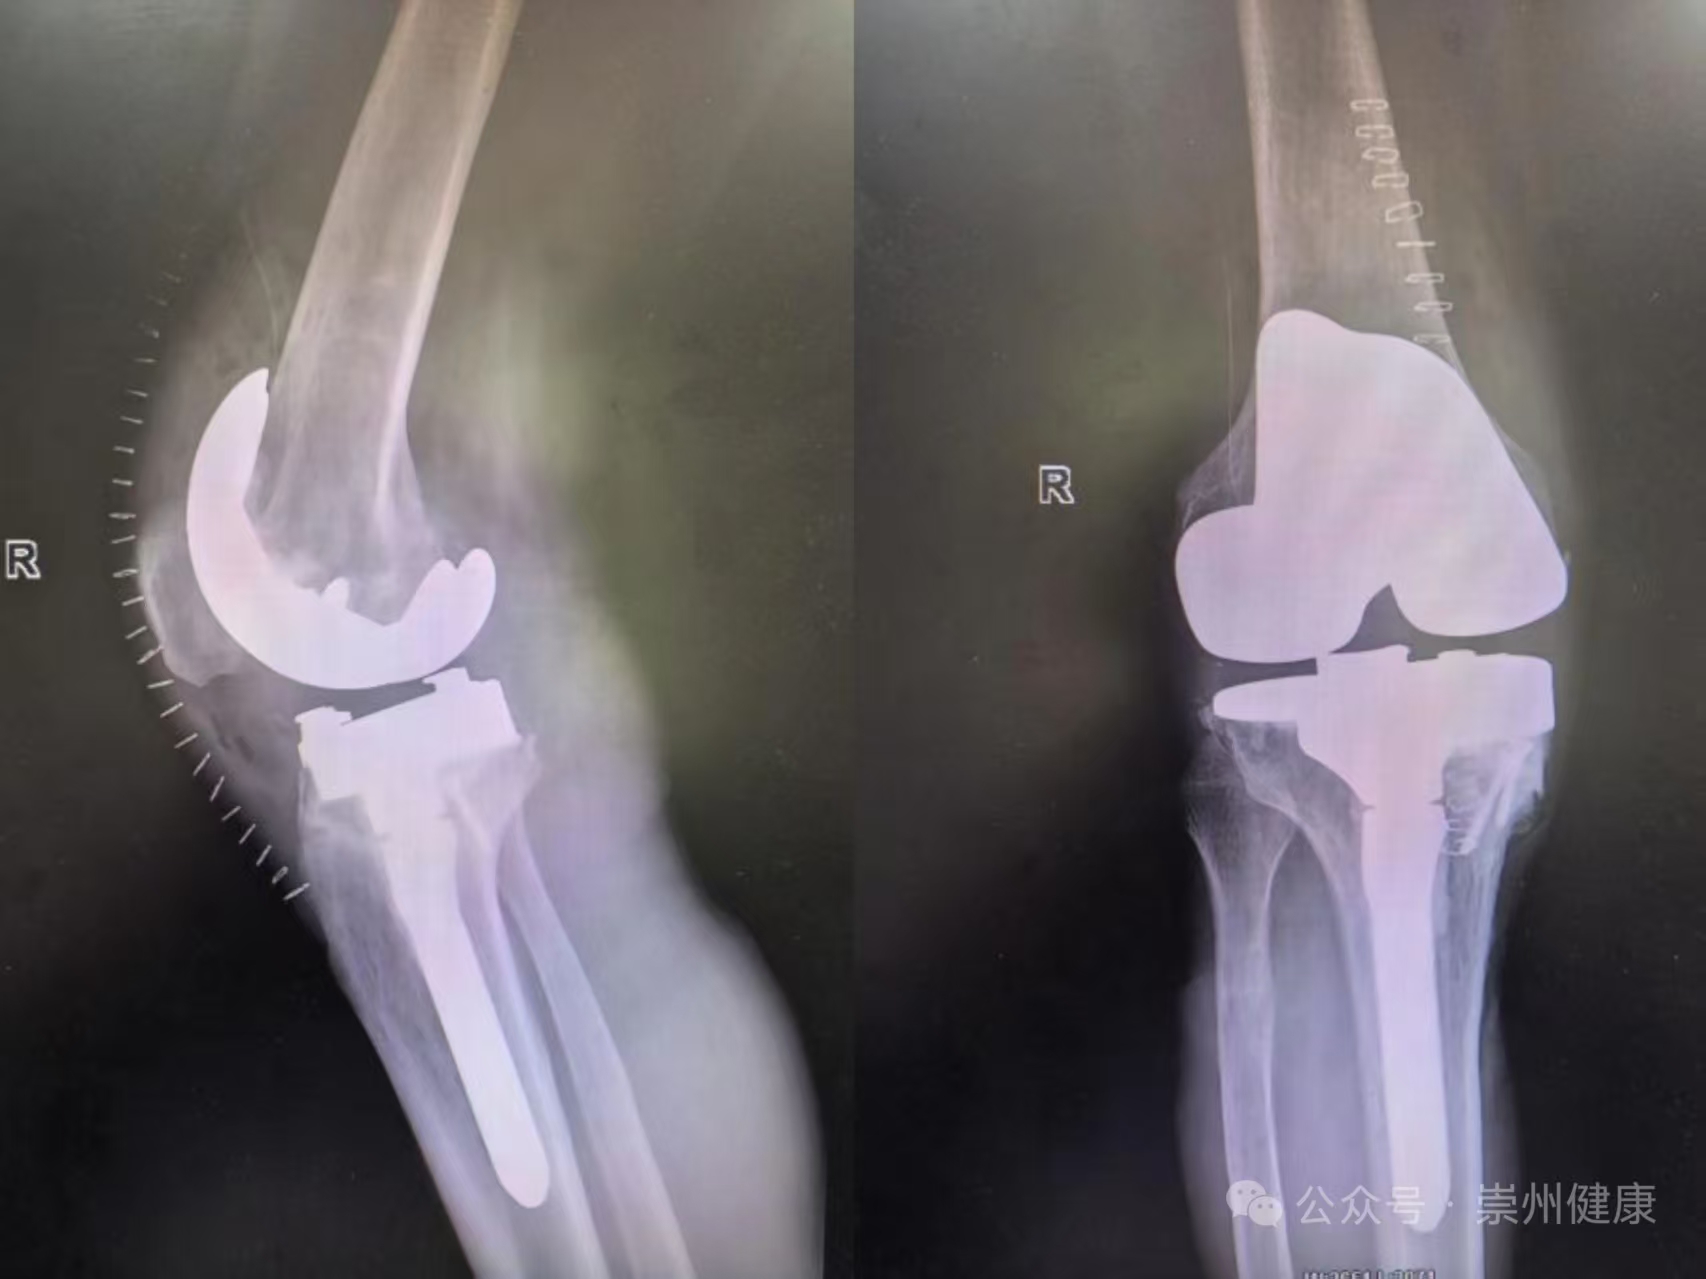

术前摄片

术后摄片